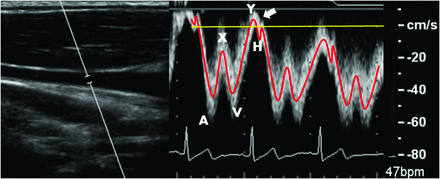

IJV flow measurement reproducibility was assessed. Similar to the analysis performed by Haacke (ms-mri.com), 3 measurement planes were placed along the length of a centerline cubic spline. Measurements were taken at the level just below the jugular bulb (upper), at the midpoint of the spline (mid), and just above the IJV junction with the subclavian vein (lower). An example 3D rendering and placement of planes along the spline are shown in Fig 2 (left). Interscan Bland-Altman 95% LOA and biases across all levels and volunteers were calculated. Figure 2 (right) shows sample IJV blood flow waveforms for each location (left), with detection of retrograde flow in the lower measurement plane. Comparing this lower waveform with a Doppler ultrasound–acquired jugular flow waveform (Fig 3), PC-VIPR is capable of resolving, both spatially and temporally, the triphasic flow waveform typical in the IJV.

Left: Example placement of measurement planes in the right IJV down a centerline cubic spline and in the left common carotid artery. Right: Blood flow waveforms over the cardiac cycle indicate increasing pulsatility proximal to the heart, with a portion of the lower waveform showing retrograde flow (arrow). A indicates atrial systole; X, atrial relaxation; V, ventricular systole; Y, tricuspid reopening; H, atrial refilling.

Left: B-mode anatomic location of right IJV blood flow. Right: Doppler ultrasonography displays triphasic IJV blood flow waveform as indicated in Fig 2. Arrow indicates minor normal reflux during the tricuspid valve reopening.

The tortuous and varied nature of the IJV causes difficulty in measuring blood flow at various locations along its length. PC-VIPR is ideal as a 4D flow measurement tool for this vascular territory. Figure 2 (left) demonstrates the use of a centerline cubic spline in the placement of measurement planes, permitting measurements orthogonal to the expected direction of flow. Figure 2 (right) reveals differing pulsatility that axial locations along the IJV exhibit. Each flow waveform is triphasic in nature. As we move closer toward the beating heart, and incidentally to locations in which the IJV is adjacent to and often physically touching the common carotid artery, the IJV exhibits greater pulsatility. The lower waveform of Fig 2 (right) exhibits retrograde flow over a short period of the cardiac cycle. The triphasic waveform is expected, corresponding to variations in carotid pulsatile motion.27 An independent Doppler ultrasonographic examination of the jugular vein (Fig 3) confirms the triphasic waveform and minor retrograde flow seen in a healthy volunteer.